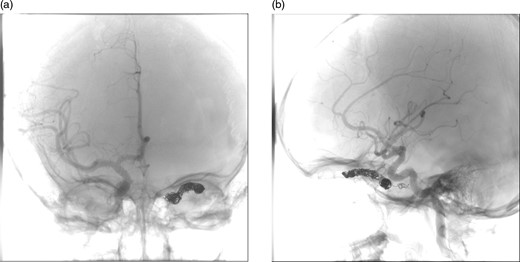

After a discussion that involved the neuroradiology team, neurosurgical team, the patient and her family, a decision was made to proceed with endovascular treatment of the fistula. Following informed consent from the patient's parents, the procedure was performed under general anaesthesia. Axis to the right common femoral artery was achieved with a 6-French micropuncture kit. A 6-French sheath was inserted into the right common femoral vein. A 6-French guide catheter was placed in the left internal jugular bulb. Thereafter, 4-French sheath was placed in the left common femoral vein. Then, a 4-French Weinberg catheter was placed in the left common carotid. A Headway microcatheter was advanced into the cavernous sinus trough the petrosal sinus into the cavernous sinus and subsequently into the dilated ophthalmic vein. Multiple coils were then placed into the ophthalmic vein throughout its course in the orbit back as far as the anterior section of the cavernous sinus. This resulted in near complete occlusion of the fistula. No immediate complications occurred, and the patient woke without any new neurological deficit in recovery (Fig. 3).

(a) and (b) Post-procedural digital subtraction angiogram under general anaesthesia shows no evidence of a residual CCF following coil embolization.